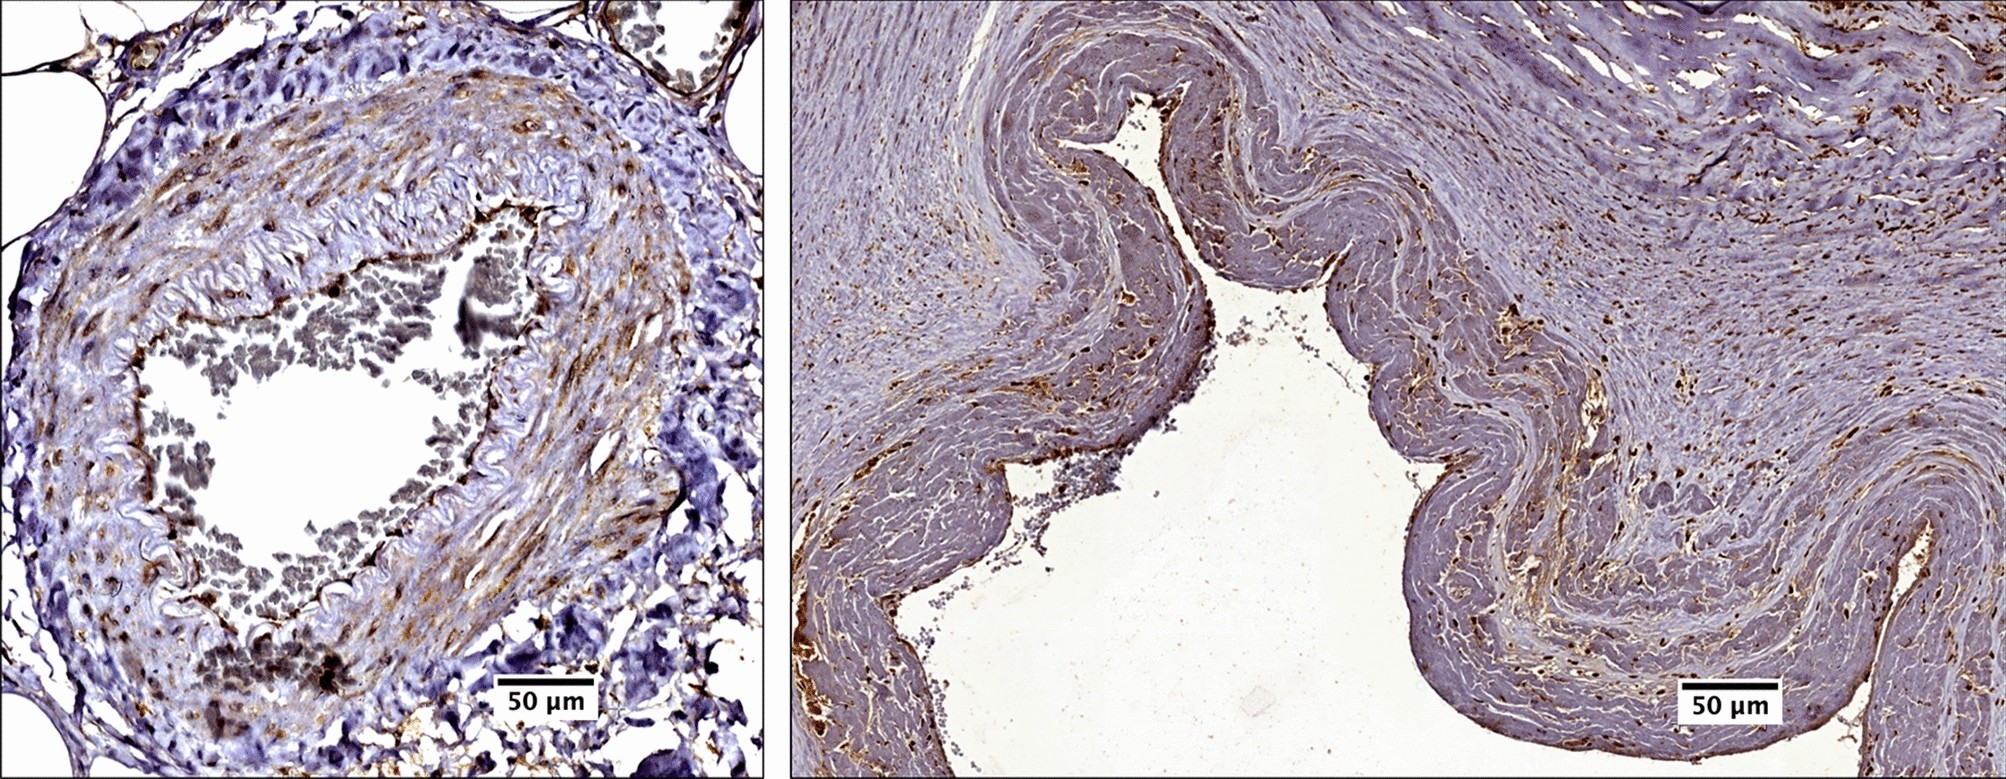

Figure 1

Immunostaining of CARD8 in non-atherosclerotic arteries. CARD8 expression was found in the endothelial layer of intima and smooth muscle cells in the media of non-atherosclerotic artery (Left: Artery from colon tissue, Magnification, × 30; Right: Popliteal artery, Magnification, × 10). Scale bar: 100 μm. Full images are available as Supplementary material.